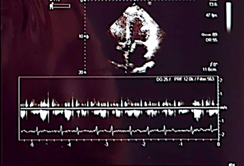

Case number 1: This is a 60-year-old male patient with a history of known hypertension for 10 years controlled with Candesartan plus hydrochlorothiazide 32/25 mg daily. Mixed dyslipidemia controlled with statin type atorvastatin 40 mg daily. Significant central obesity BMI of 35. Also, sedentary life. History of 4 inoculations with the Pfizer vaccine, he began to present with acute respiratory distress, palpitations, paroxysmal nocturnal dyspnea, orthopnea, saturation of 85% by oximetry. On physical examination: marked arterial hypotension 80/60 FC: 135 beats per minute Respiratory rate of 28 per minute acrocyanosis and on cardiac auscultation: rhythm Irregularly irregular with a more audible mitral regurgitation murmur at the apex of the heart radiating to the axilla. Lung auscultation: crackles from the middle third to the base of both lung fields. The electrocardiogram shows rapid atrial fibrillation rhythm at 135 beats per minute. Chest X-ray: Grade III-IV cardiomegaly with acute pulmonary edema. An echocardiogram was performed, showing findings compatible with dilated cardiomyopathy with left ventricular ejection fraction of 10%. Global hypokinesia, in doppler moderate-severe mitral regurgitation. Moderate-severe tricuspid regurgitation with pulmonary systolic pressure of 90 mmHg. Tissue Dopplar significant increase in left intraatrial pressure 25. In addition, the following laboratory analyzes were performed: Complete blood count: leukopenia: 2,000 leucocytes. Hb: 12.5 g/dl. Thrombocytopenia: 107,000 platelets, severe eosinopenia and lymphopenia. Elevated D-dimer 2.0 (normal value up to 0.50) Elevated NtproBNP 3,500 (normal up to 300). C-reactive protein of 32 Normal up to 10. Ferritin of 750 (normal up to 250). Creatinine: 3.2 mg/dl Urea: 70, TGO: 110, TGP:115.

Echocardiogram

Severe

1. Findings compatible with dilated cardiomyopathy secondary to graphene hydroxide

2. Severely depressed ejection fraction (10%).

3. Moderate-severe mitral regurgitation

4. Elevated left intraatrial pressure (20)

5. Ventricular filling pattern of a restrictive nature

6. Moderate pulmonary arterial hypertension

7. Fast Atrial Fibrillation Rhythm.